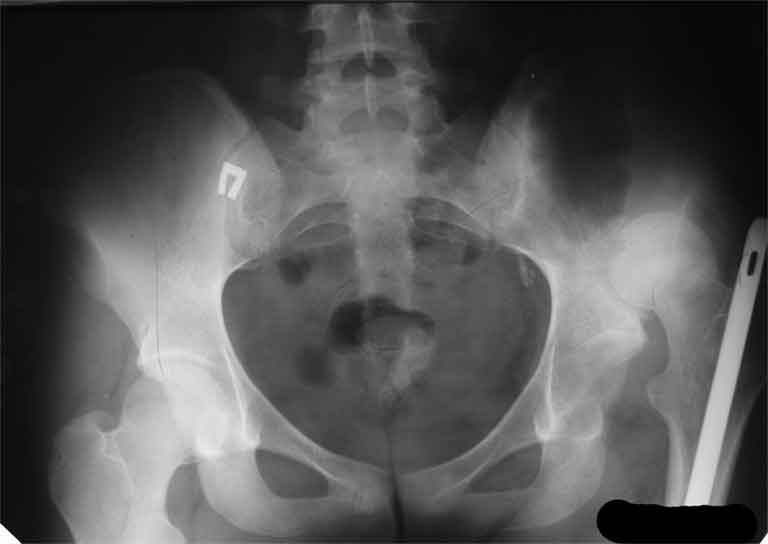

Насчет 8 см согласен с А.Н. Челноковым, это наверное ортопедическое за счет приводящей, сгибательной контрактуры и, возможно, колена. на ликвидацию укорочения у нас обычно уходит около 2-х нед. снимки в приложении, возможно не очень показательные, но других с ходу не нашел, завтра еще поищу.